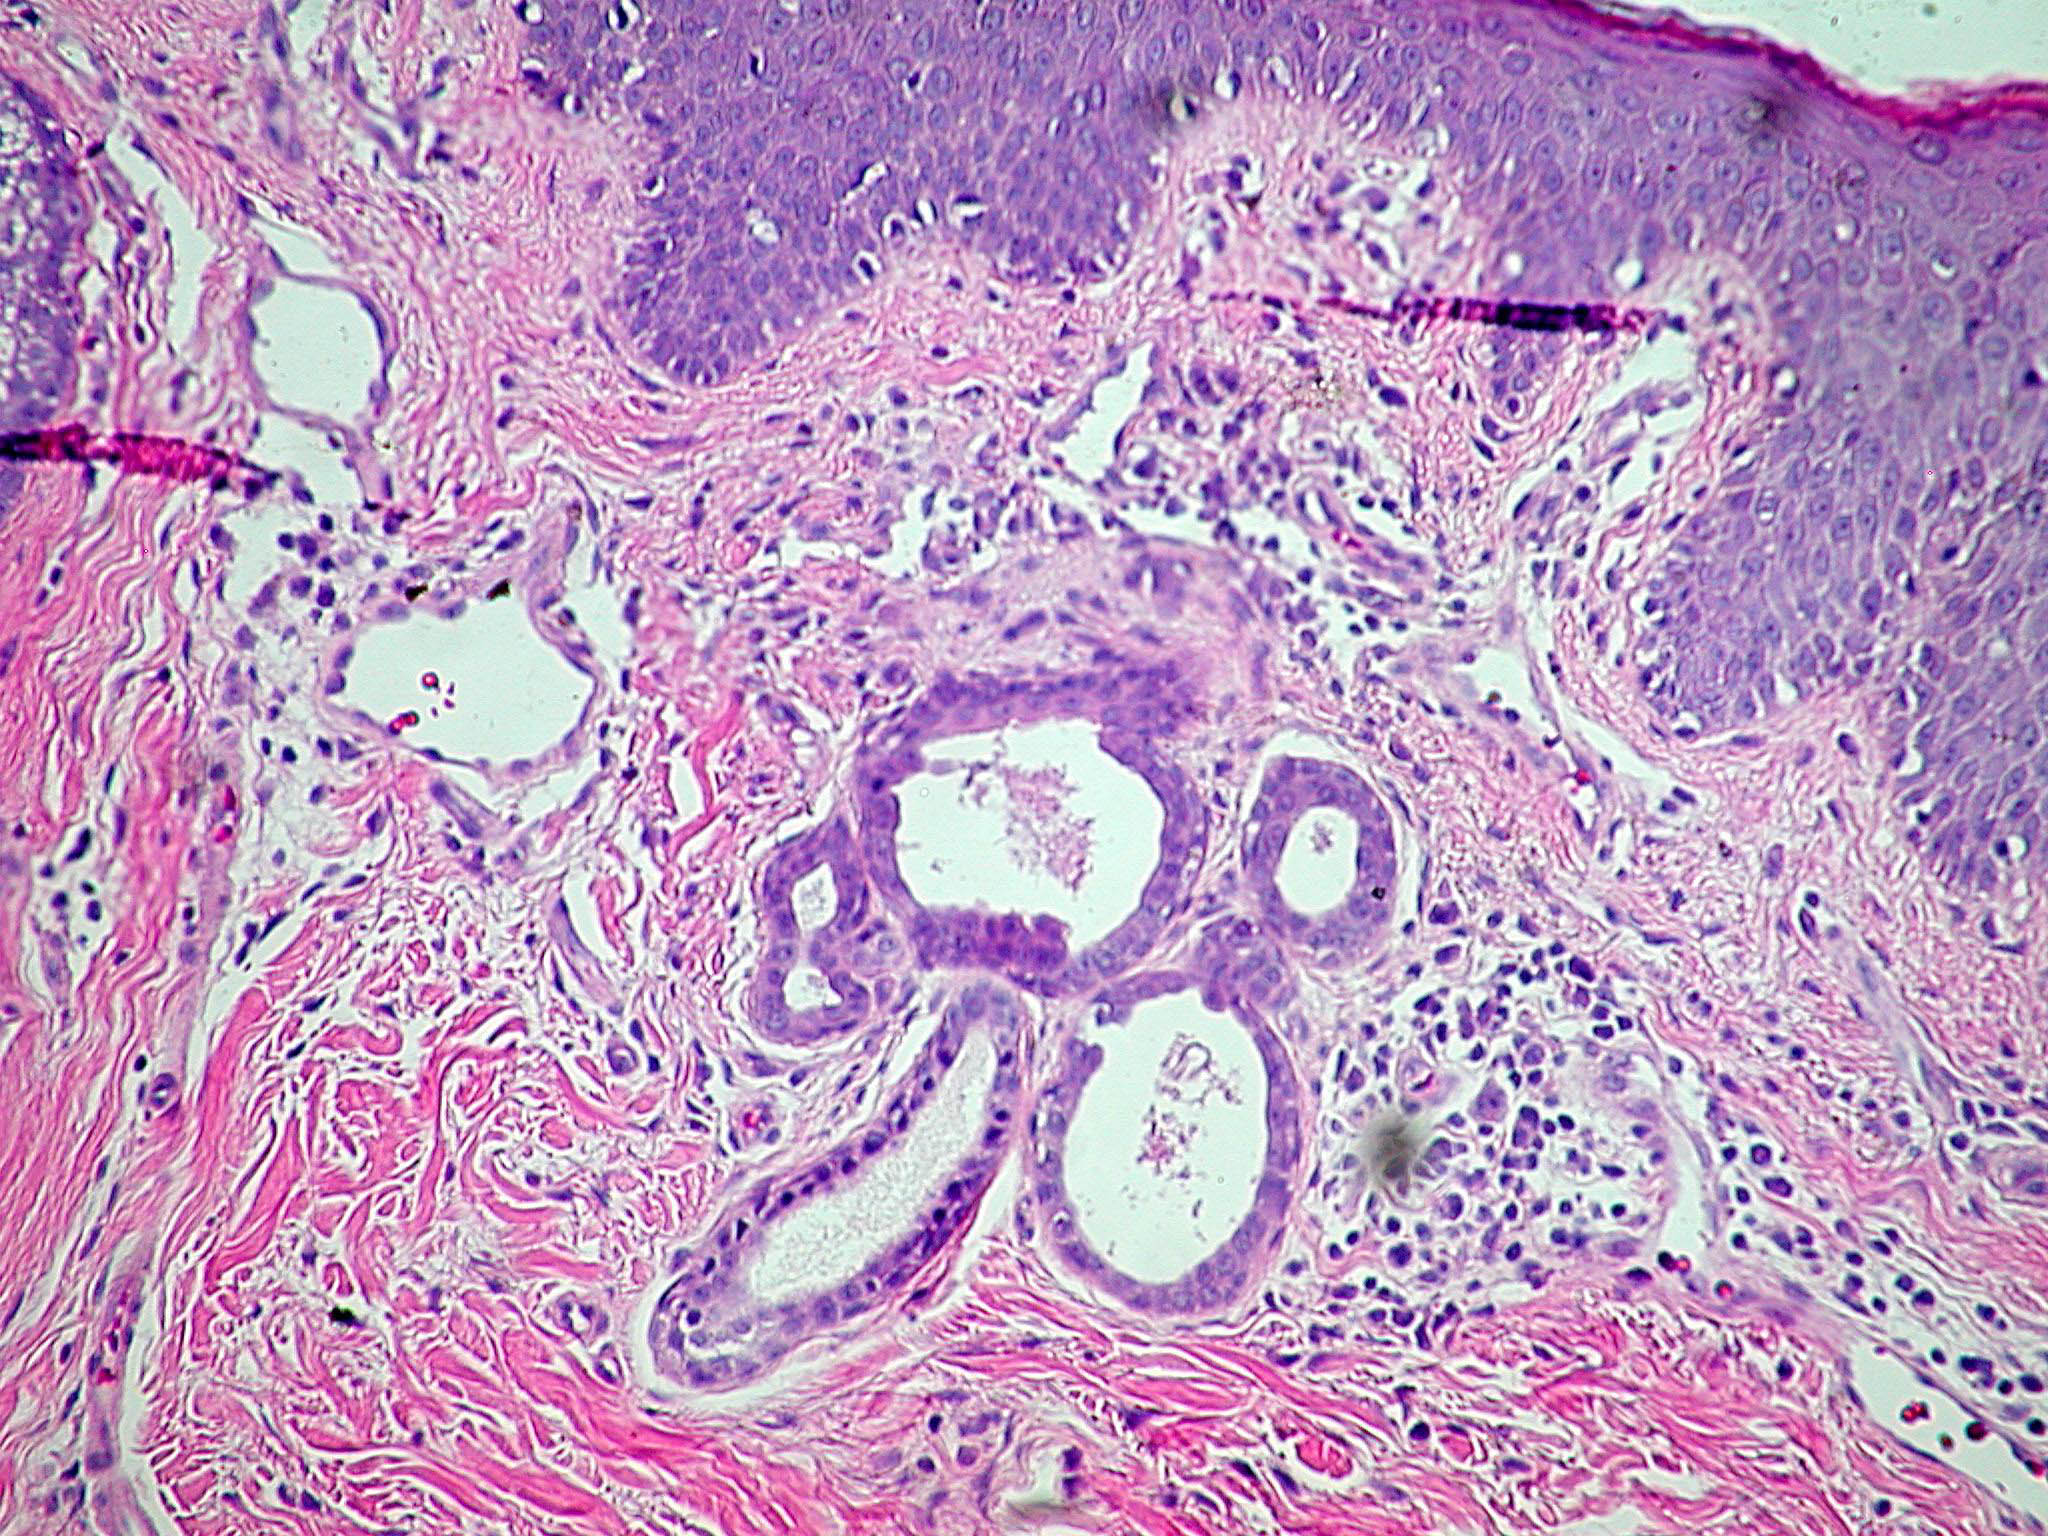

Nevus_sebaceous = الوحمة الدهنية